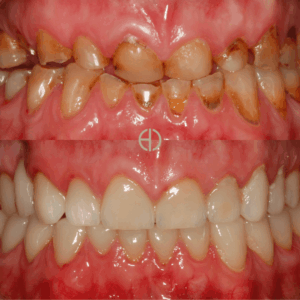

Thorough Examination of Teeth, Gum & Soft Tissues

Full-Mouth X-Rays with Extraoral and Intraoral Photographs

Dr Dana is known for her calm and thoughtful approach, She has helped even the most anxious patients feel comfortable and supported. She specialises in holistic care, implants, gum health and airway-focused dentistry.

Dr Matthew Fleming

Dr Matthew brings his deep expertise in restorative dentistry, root canal treatment and advanced smile rehabilitation. His patients trust his steady hand, clear communications and deep commitment to quality care.